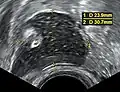

Dermoid cyst in vaginal ultrasonography Dermoid cyst in vaginal ultrasonography